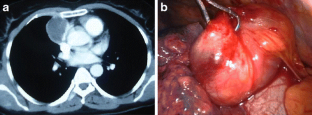

Fig. 2